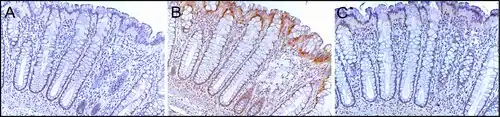

PMS2 is usually expressed at a high level in cell nuclei of enterocytes (absorptive cells) within the colonic crypts lining the inner surface of the colon (see image, panel A). DNA repair, involving high expression of PMS2, ERCC1 and ERCC4 (XPF) proteins, appears to be very active in colon crypts in normal, non-neoplastic colonic epithelium. In the case of PMS2, the expression level in normal colonic epithelium is high in 77% to 100% of crypts.[27]

Cells are produced at the crypt base and migrate upward along the crypt axis before being shed into the colonic lumen days later.[28] There are 5 to 6 stem cells at the bases of the crypts.[28] If the stem cells at the base of the crypt express PMS2, generally all several thousand cells of the crypt[29] will also express PMS2. This is indicated by the brown color seen by immunostaining of PMS2 in most of the enterocytes in the crypt in panel A of the image in this section. Similar expression of ERCC4 (XPF) and ERCC1 occurs in the thousands of enterocytes in each colonic crypt of the normal colonic epithelium.

The tissue section in the image shown here was also counterstained with hematoxylin to stain DNA in nuclei a blue-gray color. Nuclei of cells in the lamina propria (cells which are below and surround the epithelial crypts) largely show hematoxylin blue-gray color and have little expression of PMS2, ERCC1 or ERCC4 (XPF).